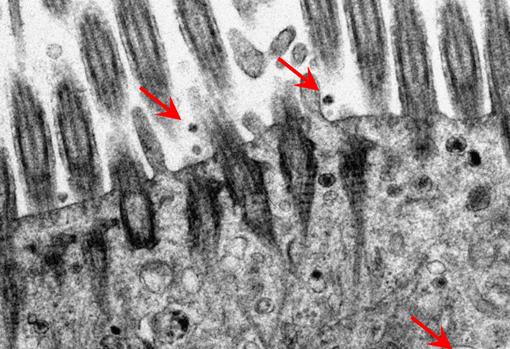

Michael Chan Chi-wai y su equipo del HKUMed han sido pioneros en el uso de cultivos ex vivo del tracto respiratorio para investigar muchas infecciones por virus emergentes desde 2007 , como la gripe aviar, el coronavirus del síndrome respiratorio de Oriente Medio (MERS).

Ahora, esta técnica se ha aplicado para comprender por qué la variante Omicron puede diferir en la transmisión y la gravedad de la enfermedad de otras variantes del SARS-CoV-2.

Este método utiliza tejido pulmonar extraído para el tratamiento del pulmón , que normalmente se desecha, para investigar enfermedades víricas del tracto respiratorio.

Los investigadores aislaron con éxito la variante Omicron SARS-CoV-2 y utilizaron este modelo experimental para comparar la infección con el SARS-CoV-2 original de 2020, la variante Delta y la variante Omicron reciente.

Así descubrieron que la nueva variante Omicron se replica más rápido que el virus SARS-CoV-2 original y la variante Delta en el bronquio humano. A las 24 horas después de la infección, la variante Omicron se replicó alrededor de 70 veces más que la variante Delta y el virus SARS-CoV-2 original.

Por el contrario, Omicron se replicó de manera menos eficiente (más de 10 veces menor) en el tejido pulmonar humano que el virus SARS-CoV-2 original, lo que puede sugerir una menor gravedad de la enfermedad.